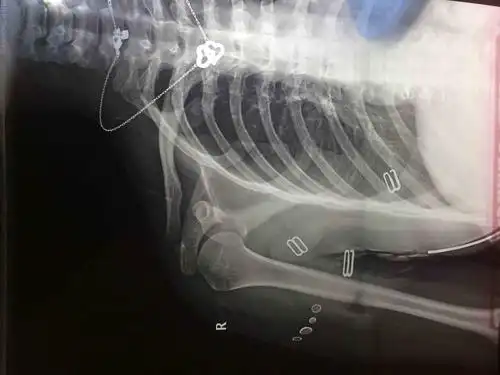

术后右肩关节正位片

关节活动受限,疼痛.诊断:肩袖损伤,腋神经损伤 病案号:1907